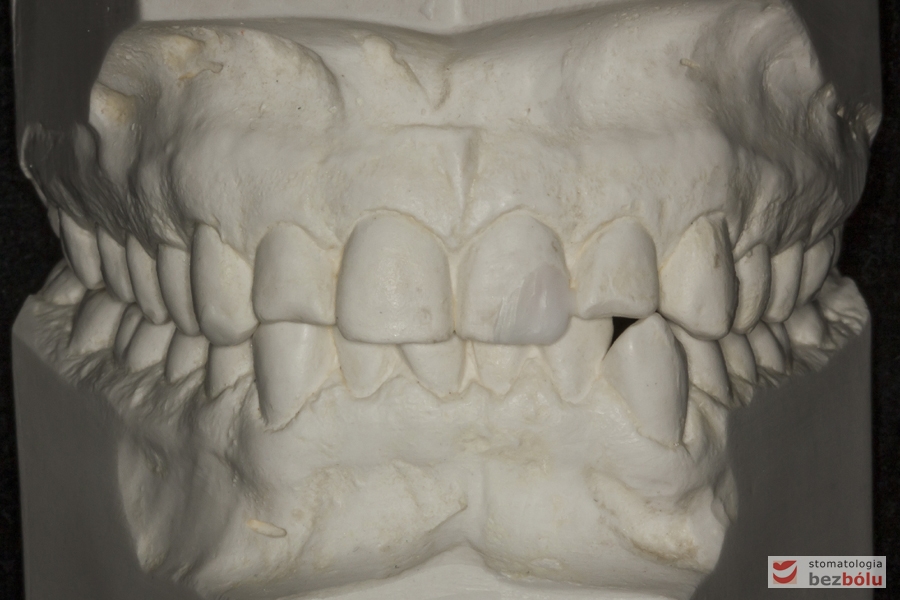

Ortodontyczne modele diagnostyczne - dla wykonania obliczeń wielkości i kształtu zębów

Ortodontyczne modele diagnostyczne – dla wykonania obliczeń wielkości i kształtu zębów